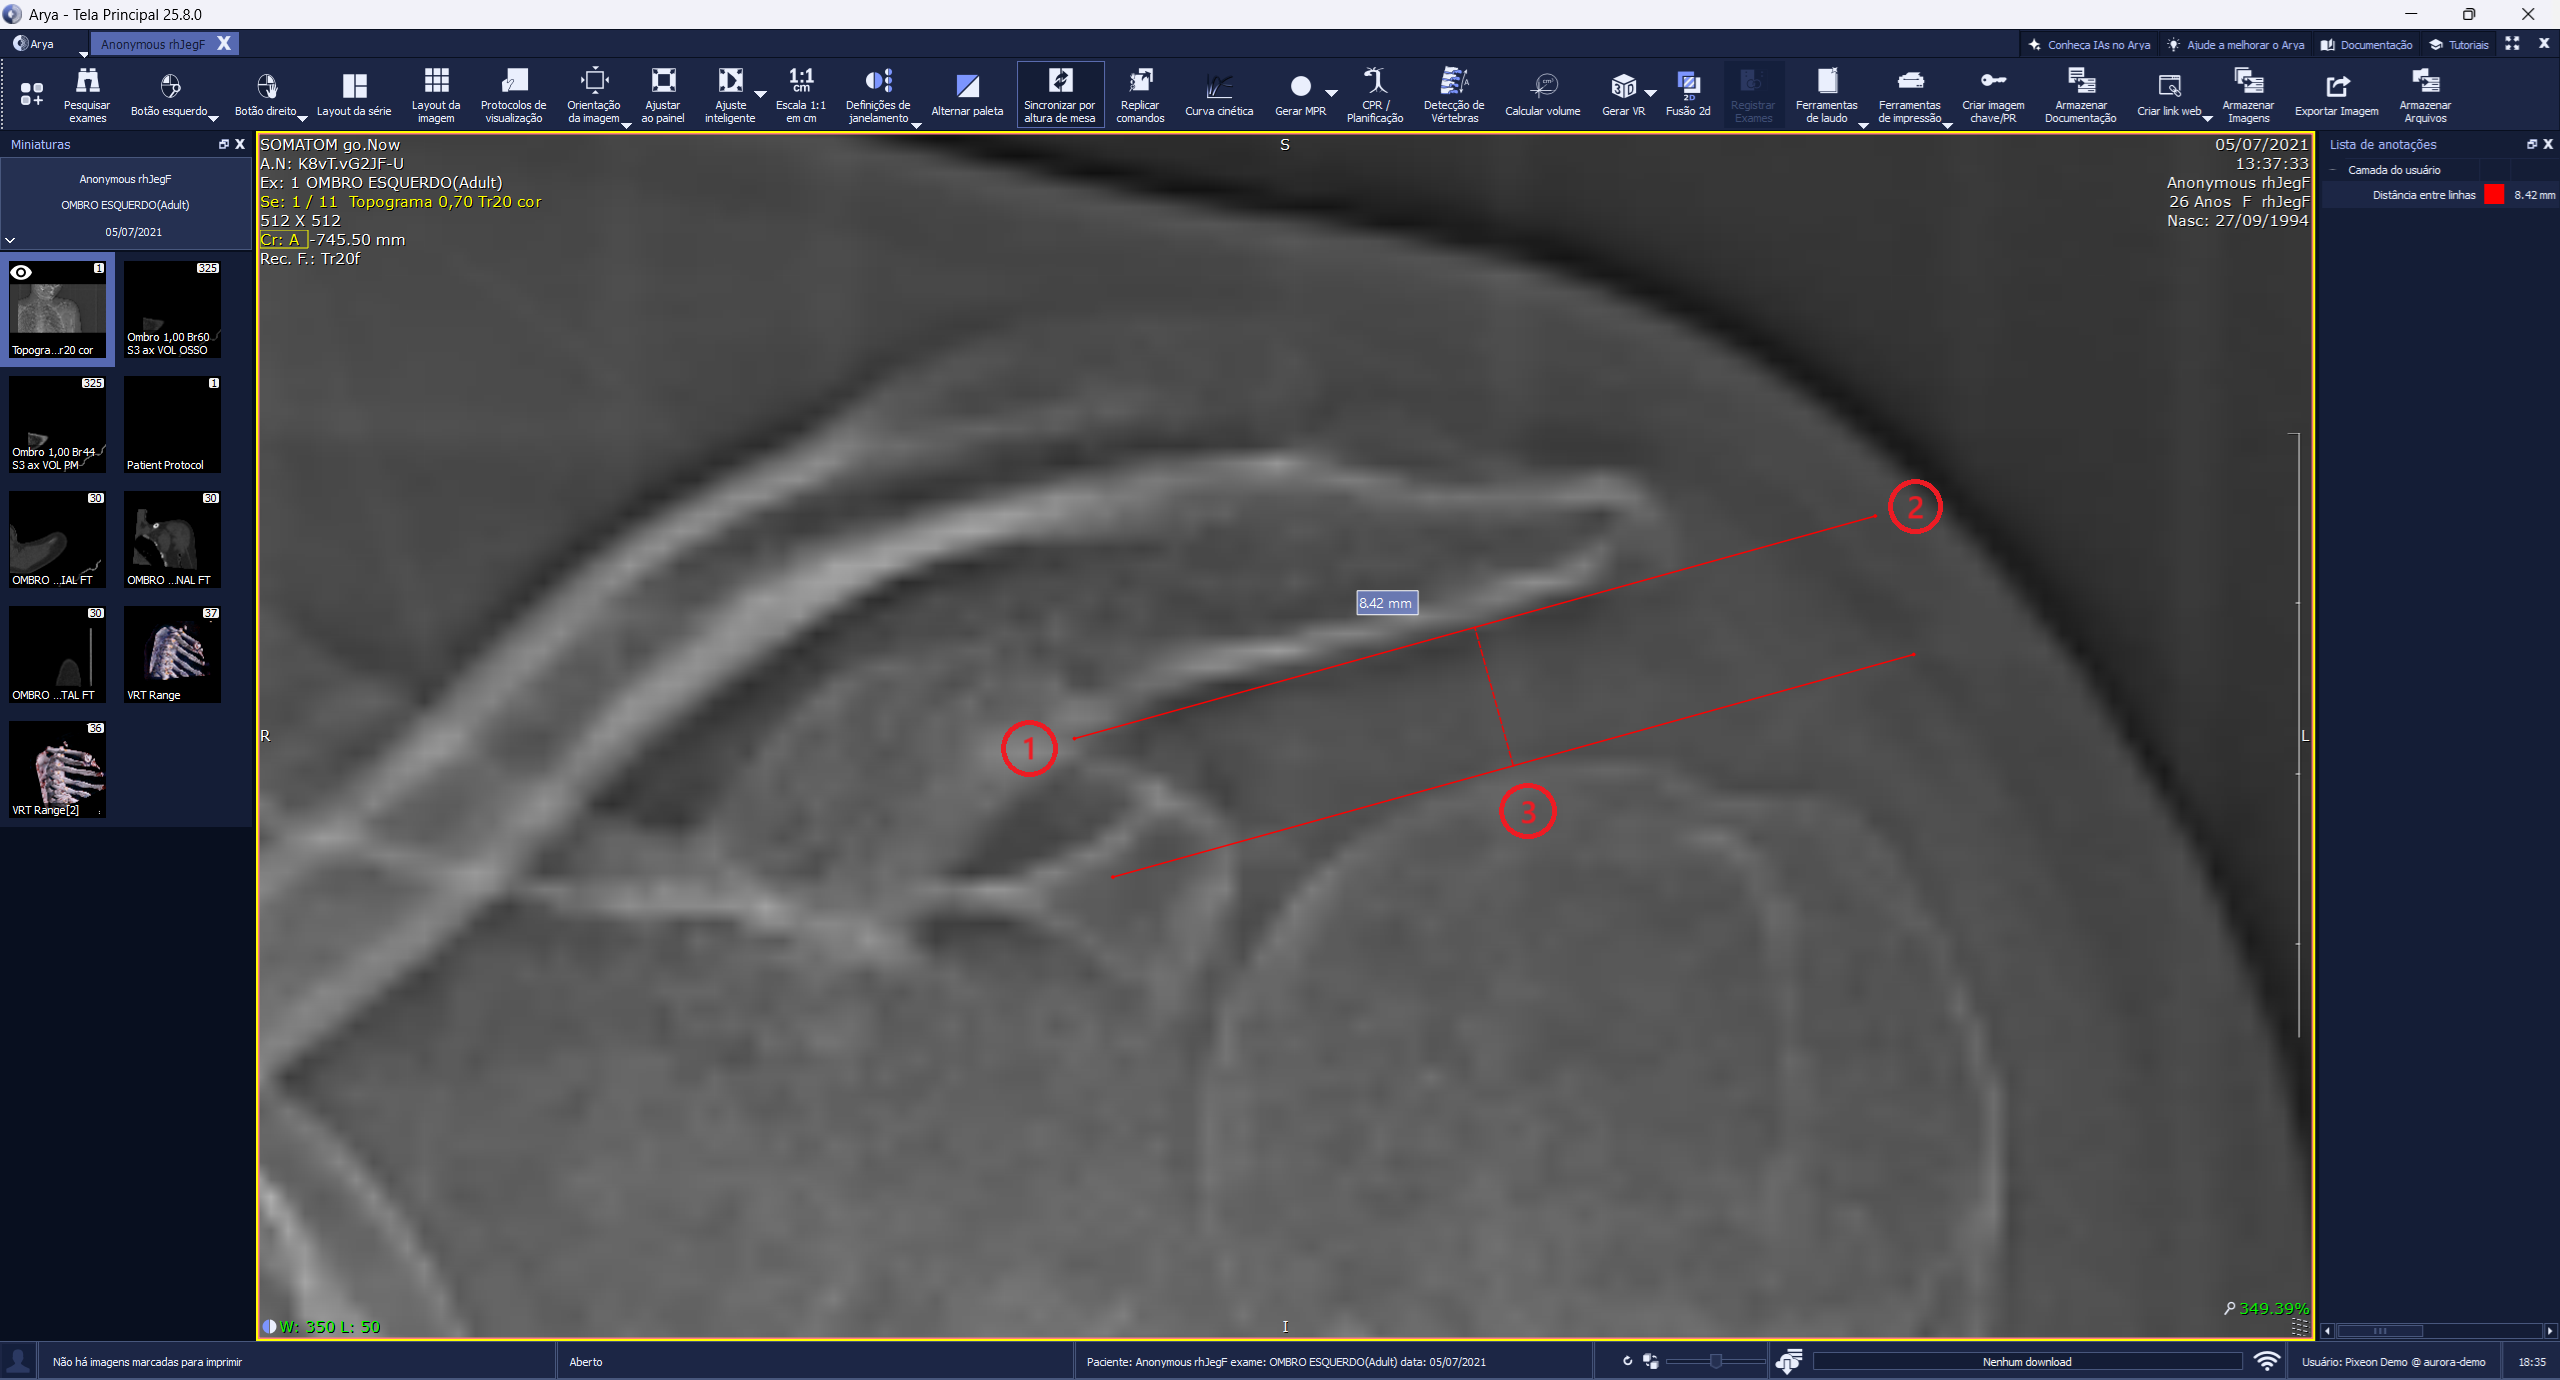

A nova ferramenta Distância Entre Linhas permite desenhar duas linhas paralelas e medir o espaçamento entre elas, sendo valiosa para verificar as distâncias acromioumeral, acromioclavicular e intra-articular do joelho, entre outras.

Com foco em gerar eficiência na análise das imagens, o cálculo é feito com apenas três cliques: os dois primeiros definem o início e o fim da primeira linha e o terceiro clique define a posição da segunda linha, registrando a distância efetiva entre as duas.

🔹 A nova medição automática da Distância entre linhas paralela de duas anatomias, trazendo agilidade na avaliação de cavidades e espaços articulares.